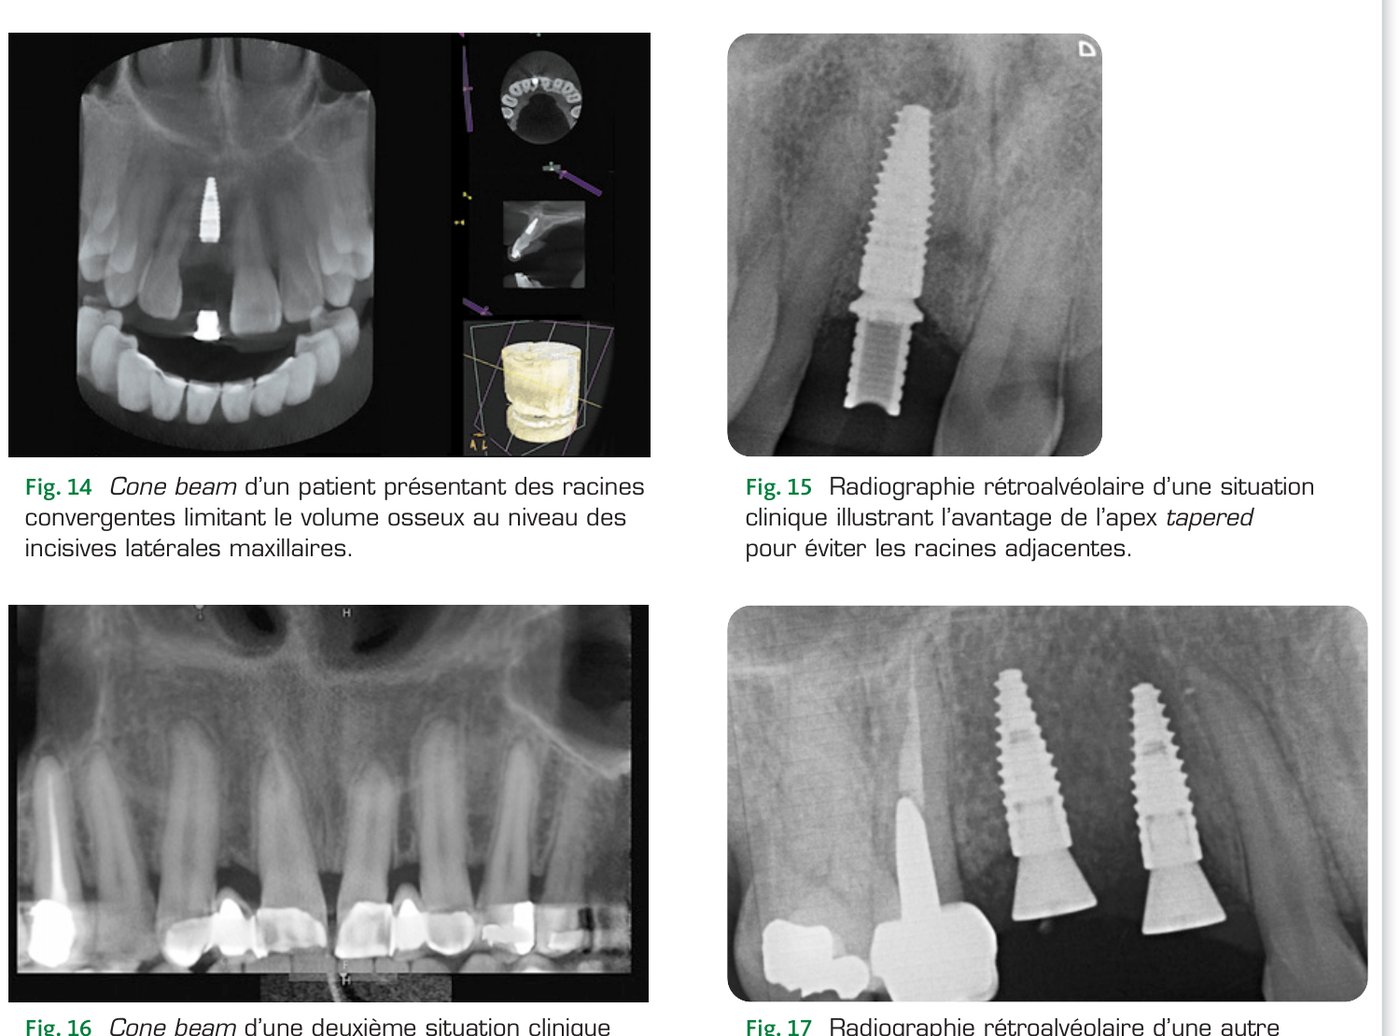

L'analyse préimplantaire comprend systématiquement une analyse radiographique. La présence de racines convergentes est détectable à la fois sur des clichés rétroalvéolaires bien angulés et à l'examen tomodensitométrique (Fig. 14). Le volume osseux disponible pour l'implantation est parfois réduit par la présence de racines adjacentes convergentes. Une lésion du cément ou de la dentine provoquée par le forage ou par l'implant peut déclencher un processus de résorption externe, entraîner une fêlure ou une fracture ou encore la nécrose de la dent concernée.

Un volume résiduel trop faible pour placer un implant sans garantir une distance de sécurité avec les obstacles anatomiques est une contre-indication locale à la pose d'implants dentaires, il est alors nécessaire de réaliser un traitement orthodontique préimplantaire. Certaines situations sont moins tranchées, le recours à un implant ayant une conicité apicale permet de gagner de l'espace et de placer l'implant dans la position désirée dans les trois plans de l'espace tout en évitant les racines des dents adjacentes. Le BLT présente une longueur constante de son apex conique sur les cinq derniers millimètres qui permet d'augmenter la sécurité lors de l'implantation dans ce type de situation (Fig. 15 à 17).

Situation clinique 1 — Cone beam et radiographies illustrant la gestion des racines convergentes (Fig. 14 à 17)